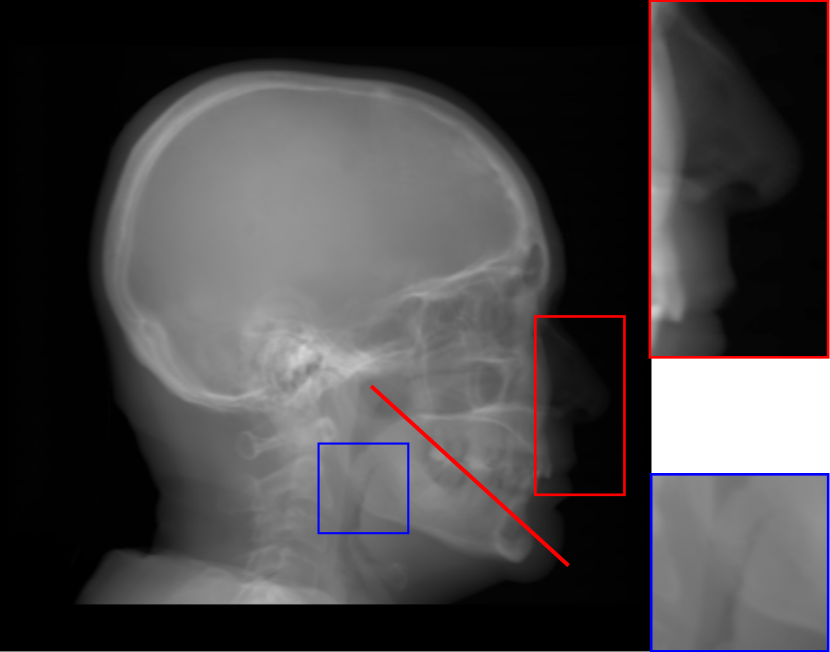

Refer to caption

(a) Real cephalogram

(b) Synthetic cephalogram

(c) Plot of samples and sigmoid curves

Fig. 2: Image contrast difference between real conventional cephalograms and RayCast synthetic cephalograms: (a) a real cephalogram example; (b) a RayCast synthetic cephalogram example; (c) the plot of samples between RayCast synthetic cephalograms and real cephalograms with an original sigmoid curve (red) and our proposed modified sigmoid curve (blue).

In Fig. 2, one real conventional cephalogram example and one example of 𝒈𝒈\boldsymbol{g} are displayed, where evident image contrast difference between these two images is observed. It is because the X-ray films used in conventional cephalograms have the special nonlinear optical property that the characteristic curve between optical density and logarithmized X-ray exposure has a sigmoid-like shape [42]. According to the Lambert-Beer law, the logarithmized X-ray exposure is equivalent to the attenuation integral. It indicates that the intensity relation between the desired cephalogram and the attenuation integral image 𝒈𝒈\boldsymbol{g} should also exhibit a sigmoid-like curve. Therefore, to make the image contrast of synthetic cephalograms similar to conventional cephalograms, a sigmoid intensity transform is necessary.